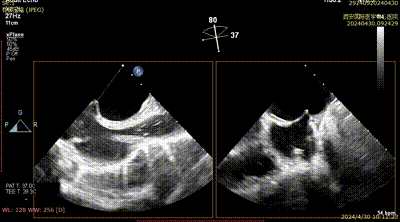

Case 1影像资料

房间隔穿刺

二尖瓣夹系统植入

二尖瓣夹瓣上Trajectory

二尖瓣夹进入左室

二尖瓣夹捕获瓣叶

二尖瓣夹夹闭

术后二尖瓣反流评估

术后结果